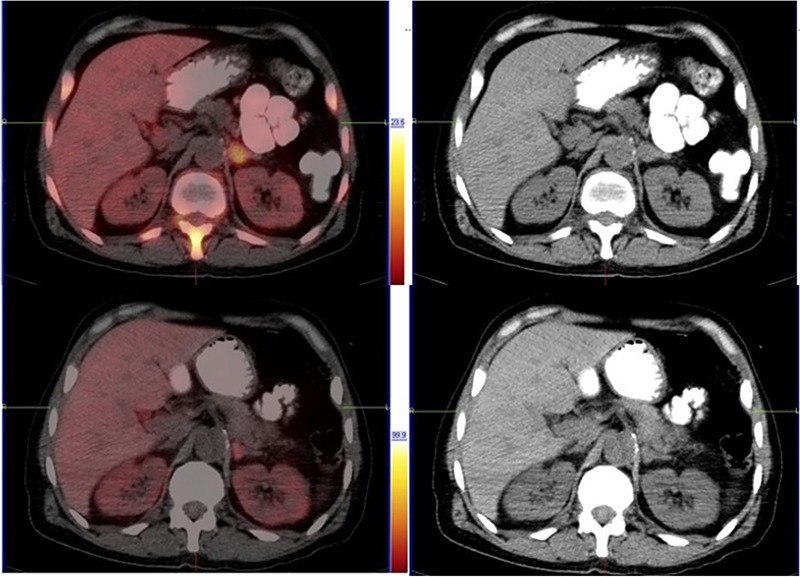

Prostate cancer typically follows a characteristic pattern of metastatic spread to the pelvic lymph nodes and bone. Atypical patterns of metastasis are rare but have been documented. In African men, this disease tends to follow a more aggressive course, with the possibility of an atypical site of metastatic spread. We present a case of a 58-year- old African male with metastatic castrate-resistant prostate cancer who presented with both typical and atypical patterns of metastatic disease detected by a fluorine 18 prostate-specific membrane antigen positron emission tomography/computed tomography scan. This patient also had a good response to radioligand therapy.